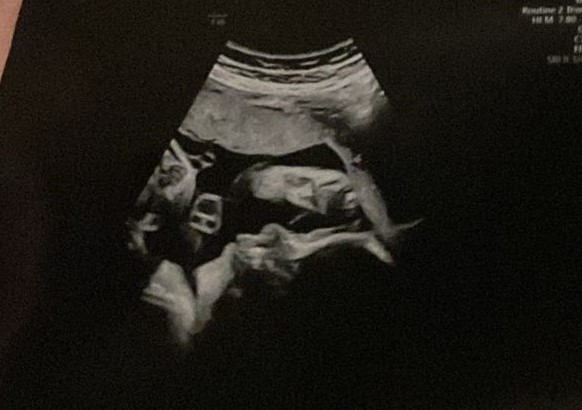

Deze week stond ons niet zo’n leuk avontuur te wachten, maar gelukkig viel het achteraf mee. Ik schreef afgelopen zaterdag al over het overslaande hartje van de baby. Hiervoor kregen we een GUO, een heel uitgebreide echo. Kindlief is net zijn of haar vader, want iedere keer als de gynaecoloog het gezichtje in beeld probeerde te brengen, vloog er weer een handje of voetje voor. De foto moet wel het gezichtje voorstellen, van de zijkant gezien. Daarnaast nog een klein avontuur waar ik reuzetrots op ben: ik ging boodschappen doen en parkeerde de auto achteruit in. Geen grootse uitdaging omdat er verder geen auto’s op dat stukje parkeerterrein stonden, maar als je bedenkt dat ik tot een paar maanden geleden het schakelen bijna was verleerd, vind ik het een hele prestatie.

Ondanks dat Kindlief graag verstoppertje speelt, is het wel een mooie echo. Je ziet toch al een beetje zijn of haar gezicht. 🙂